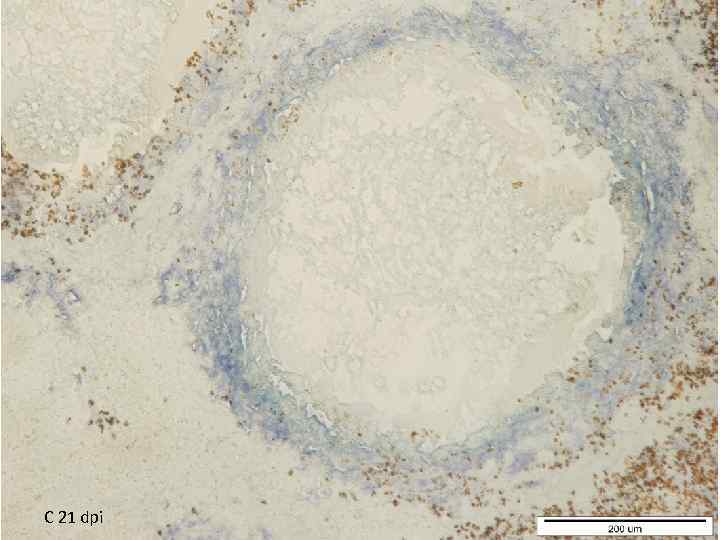

C 21 dpi